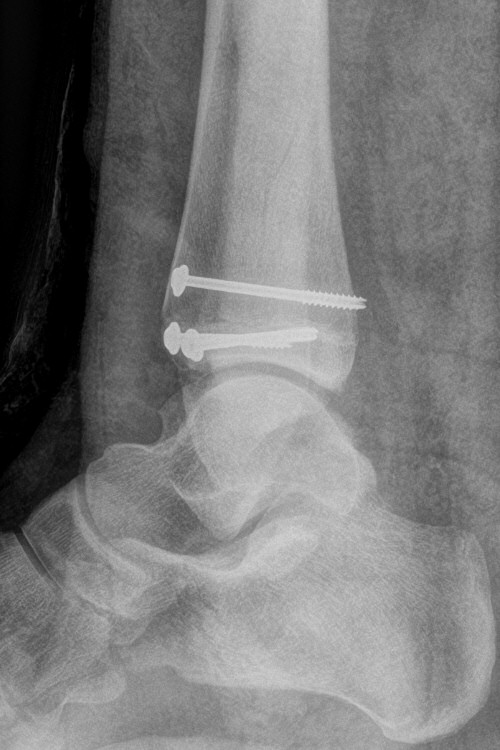

Exempel på triplansfraktur hos nästan färdigvuxet barn

Efter operation med skruvfixation

- Förbered för inläggning och snar operation, ofta med kanylerade skruvar. [2]